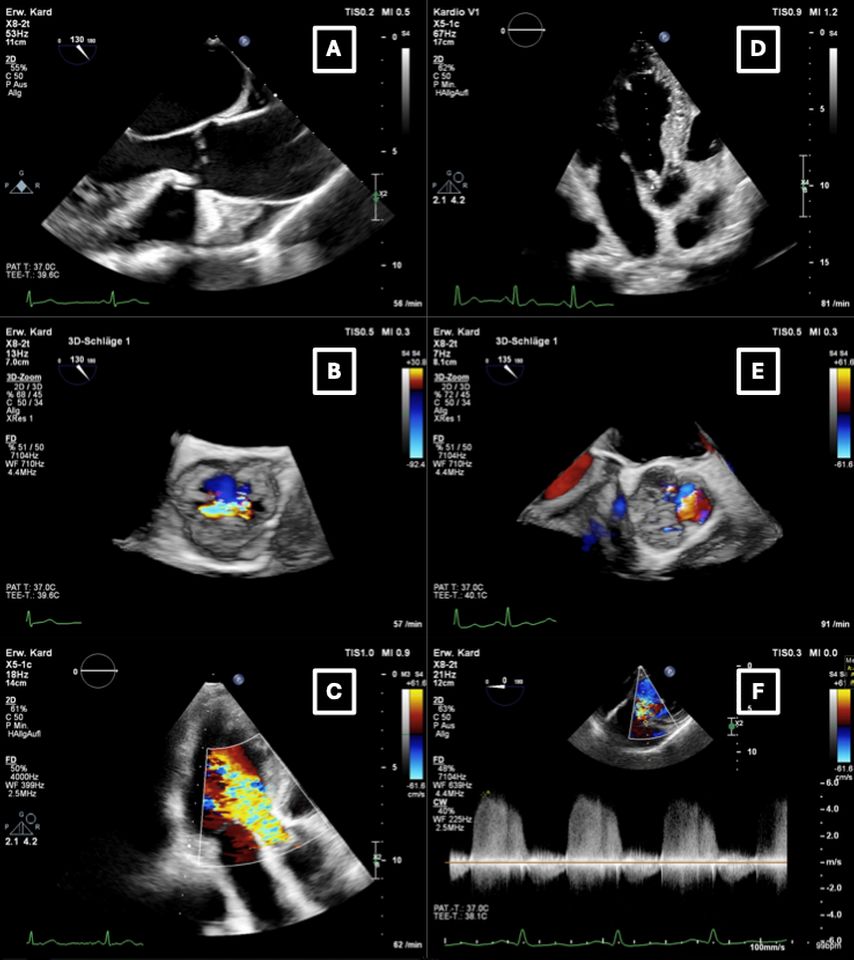

Abb. 1: Typische echokardiografische Befunde bei chronischer (A,B,C) und akuter Aortenklappeninsuffizienz (D,E,F). A,B,C: TEE bei chronischer mittel- bis hochgradiger AI mit dilatierter Aorta asc. (A) und zentralem Insuffizienzjet in der 3D-TEE (B). Im TTE zeigte sich ein breiter Insuffizienzjet im 3-Kammer-Blick (C). D,E,F: akute AI bei Endokarditis mit Vegetation im Bereich der linkskoronaren Tasche (D) und ebendort lokalisiertem Insuffizienzjet in der 3D-TEE (E). Im CW-Doppler ergab sich eine „pressure half-time“ (PHT) von ca. 230ms (F) – einer mittel- bis hochgradigen AI entsprechend